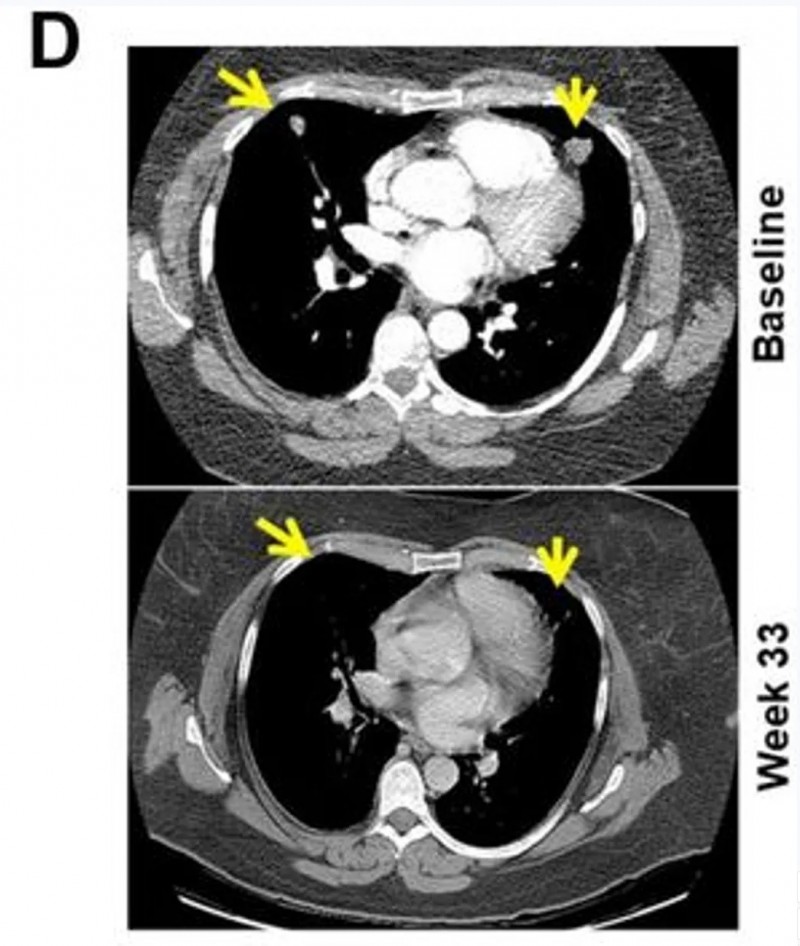

一项发表在《癌症免疫治疗杂志》上的前瞻性II期试验(NCT01876212)为联合治疗提供了证据。该研究针对15例PD-1抑制剂耐药的晚期黑色素瘤患者,使用“树突状细胞疫苗+达沙替尼”方案。

结果显示:从一开始就联合用药的B组,疗效远优于后期才联合的A组:客观缓解率达到66.7%,中位总生存期延长至15.45个月(对比3.47个月)。

▲图源“JITC”,版权归原作者所有,如无意中侵犯了知识产权,请联系我们删除

值得一提的是,B组2例代表性患者经联合治疗后,内脏转移瘤明显缩小,并产生了协同免疫反应,最终达到客观部分缓解(PR)标准。